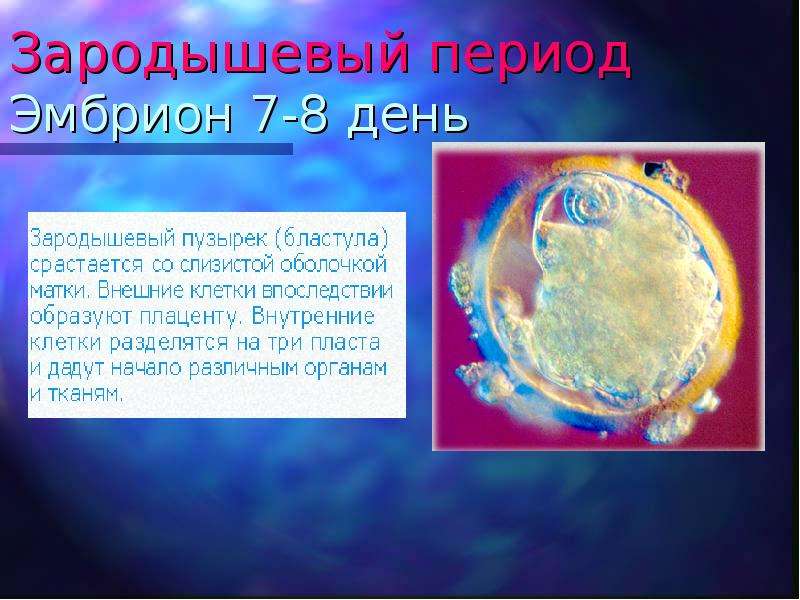

Эмбриональный период: Развитие эмбриона от зачатия до рождения